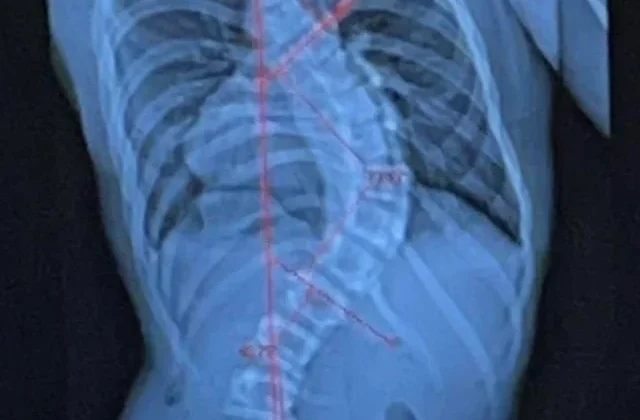

اعوجاج العمود الفقري هو انحناء غير طبيعي في العمود الفقري يجعل الظهر يبدو مائلًا إلى أحد الجانبين. وقد يكون الانحناء بسيطًا وغير ملاحظ، أو شديدًا ومؤثرًا على وظيفة الرئتين والقلب. يُصنَّف إلى أنواع عدة:

نعم، تشير الدراسات الحديثة إلى أن الانحناء الشديد في الجزء العلوي من العمود الفقري، خصوصًا في الحالات التي تتجاوز فيها زاوية الاعوجاج 70-80 درجة (زاوية كوب)، قد يسبب ضغطًا على القلب والرئتين. هذا الضغط الميكانيكي يمكن أن يعيق وظائف القلب ويؤدي إلى مضاعفات خطيرة مع مرور الوقت.